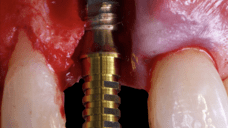

The surgical protocol began with the atraumatic extraction of tooth 1.1 to preserve as much of the alveolar socket as possible. Immediately following extraction, an N1 implant was placed into the socket using a guided surgical approach to ensure ideal three-dimensional positioning. The “one abutment one time” technique was applied to minimize soft tissue manipulation during the healing phase, which is particularly important in esthetic areas.

Given the significant buccal defect, guided bone regeneration (GBR) was performed simultaneously. A mixture of autologous bone and creos™ xenogain™ was applied to the defect and covered with a resorbable creos™ membrane to restore ridge width and support the buccal contour. In addition, a connective tissue graft was harvested and placed in the vestibular region to increase the thickness of keratinized mucosa. This combined approach addressed both hard and soft tissue deficiencies, providing the biological foundation for a stable and esthetic outcome.